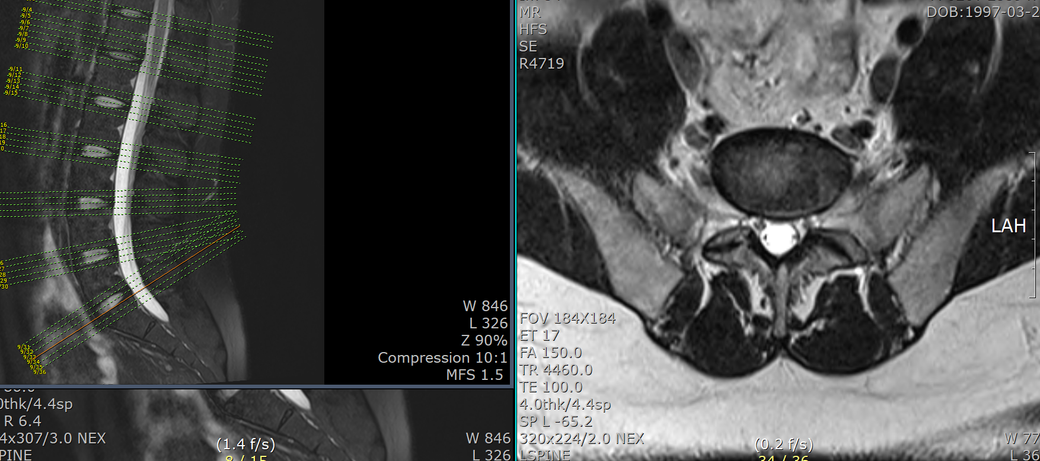

mri 판독 결과 남깁니다..

Clinical information: back pain

Pulse sequences

- T2WI and T1WI sagittal, T2WI and T1WI axial

- T2WI fat suppression sagittal

- T2WI coronal

- T2WI whole spine sagittal image

- contrast: (-)

T12-L1 level에서 disc가 뒤쪽 Lt. central aspect로 protrusion되어 있고 mild한 dural sac indentation을 주고 있음.

그 외 disc level과 neural foramen에서 definite한 abnormality는 보이지 않음.

Vertebral body의 SI, shape, 그리고 alignment도 정상이며, scanned TL-spinal cord내에 definite한 abnormal signal intensity는 보이지 않음.

• 1번 째 사진

아래 사진에 있는 부위가 아마 T12/L1 사이에 디스크가 살짝 뒤로 빠져있다는 부위이실겁니다.

옆에서 보면 두번째 사진이구요.